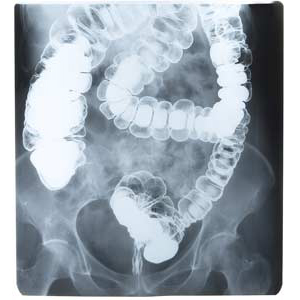

Barium sulfate is commonly used as a contrast agent in medical imaging procedures such as:

Barium swallow tests

Upper GI series

Barium enemas

While barium sulfate is considered poorly absorbed, research shows that retention and exposure still matter, particularly with repeated procedures or compromised gut integrity.

In some cases, long-term retention has been linked to granuloma formation in the colon, including the transverse colon.